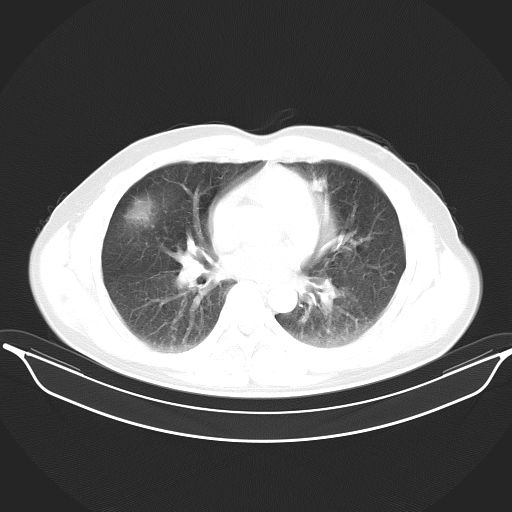

标题: CT25490:男,40岁,体检发现;无其它不适。 [打印本页]

标题: CT25490:男,40岁,体检发现;无其它不适。

倾向于结核

多考虑结核。

考虑结核

考虑肺霉菌病。

考虑右下肺周围性肺癌并肺内多发转移,纵隔淋巴结转移!

支持 !考虑右下肺周围性肺癌并肺内多发转移,纵隔淋巴结转移,(气管前腔静脉后,隆突下,主动脉弓下都有了)